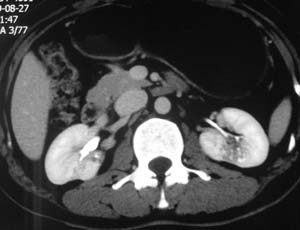

以下是引用子期在2010-3-19 20:47:00的发言:[br]血管畸形的ct增强应该有明显强化,本例并不相符合。本例双肾局部的略低密度影,累及肾盂,局部皮质明显变薄、内陷,增强扫描有轻度的强化,应考虑为炎性病变,患者为年轻男性,累及双肾的感染以结核较常见,可以没有明显的临床症状,尿中有时候也并不能查出什么;肾脓肿常有明显感染中毒症状,本例不符,另外一般的肾盂肾炎或肾小球肾炎通过小便就可确诊,其它还不能排除的是黄色肉芽肿性肾盂肾炎,然而单凭ct一般也很难鉴别。